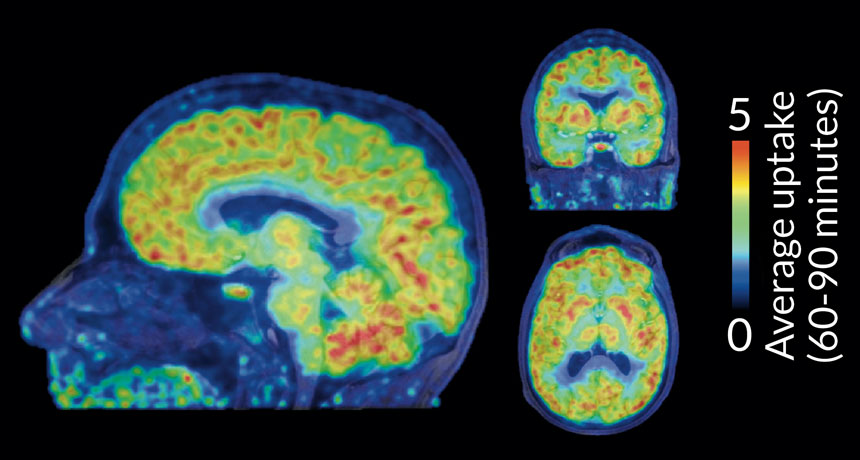

LEAVING A MARK A new radioactive tracer molecule shows where chemical tags, called epigenetic marks, are made in the brains of healthy people. Shown is the epigenetic activity in a volunteer’s brain imaged 60 to 90 minutes after injection of the tracer.

H.-Y. Wey et al./Science Translational Medicine 2016